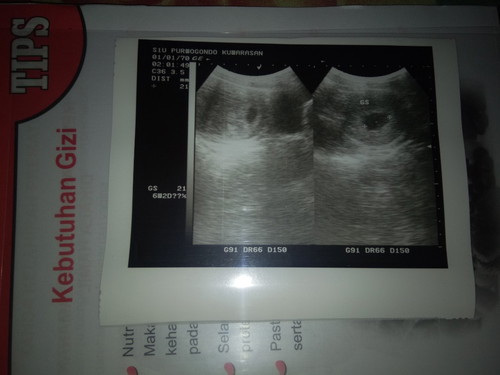

HAMIL 6 minggu

Saya hamil ke 2 jalan 6 minggu setelah hamil yang pertama kuret karena keguguran,saya udah usg tapi hasilnya kata dokter bagus dan wajar . Tapi yang saya keluhkan kenapa setiap saya kecapean selalu keluar darah yang lumayan banyak .apa itu normal ?